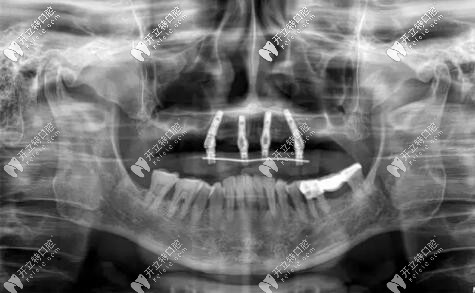

惠先生種植方案:前期ALL-ON-4即刻負(fù)重,后期上頜竇外提升,同期植入兩顆種植體,做ALL-ON-6,馬龍一體橋。

目前已完成ALL-ON-4即刻負(fù)重,通過手術(shù)情況來看,效果確實比較好,作為一位地道老陜?nèi)耍菹壬母屑ぶ橐缬谘员怼?/p>

修復(fù)后